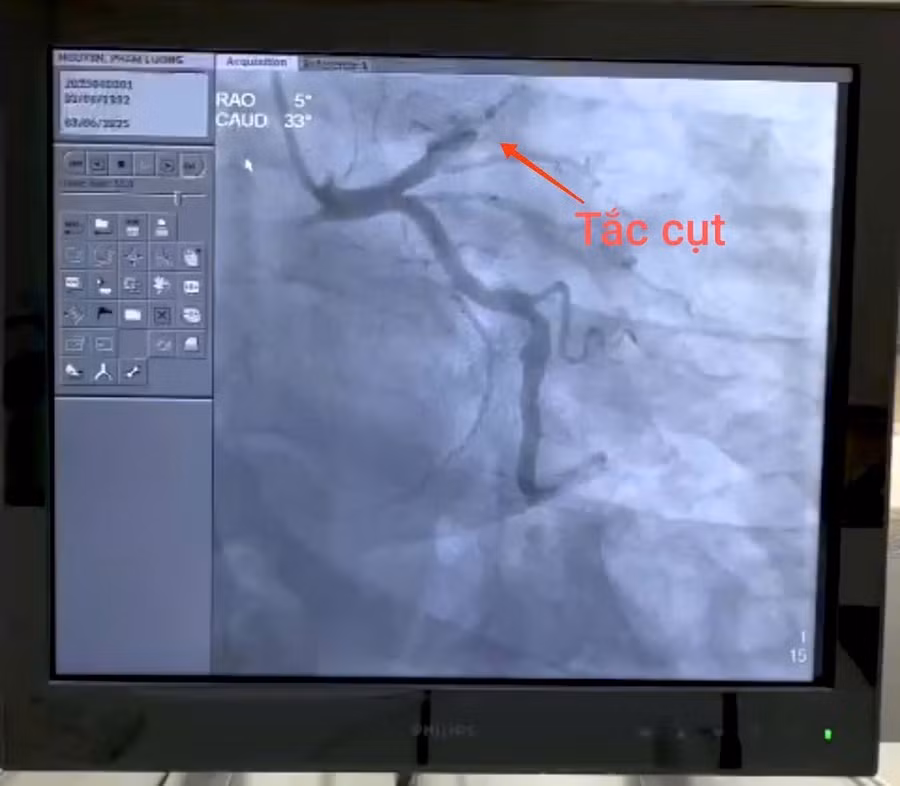

Hình ảnh cho thấy, bệnh nhân bị nhồi máu cơ tim, gây tắc nghẽn hoàn toàn từ đoạn 1, động mạch liên thất trước. Ảnh: BVCC

Tại bệnh viện, các bác sĩ xác định bệnh nhân bị nhồi máu cơ tim cấp. Bệnh nhân được chụp động mạch vành qua da. Kết quả cho thấy, huyết khối gây tắc hoàn toàn động mạch liên thất trước từ đoạn I (một động mạch chính cấp máu nuôi cơ tim).